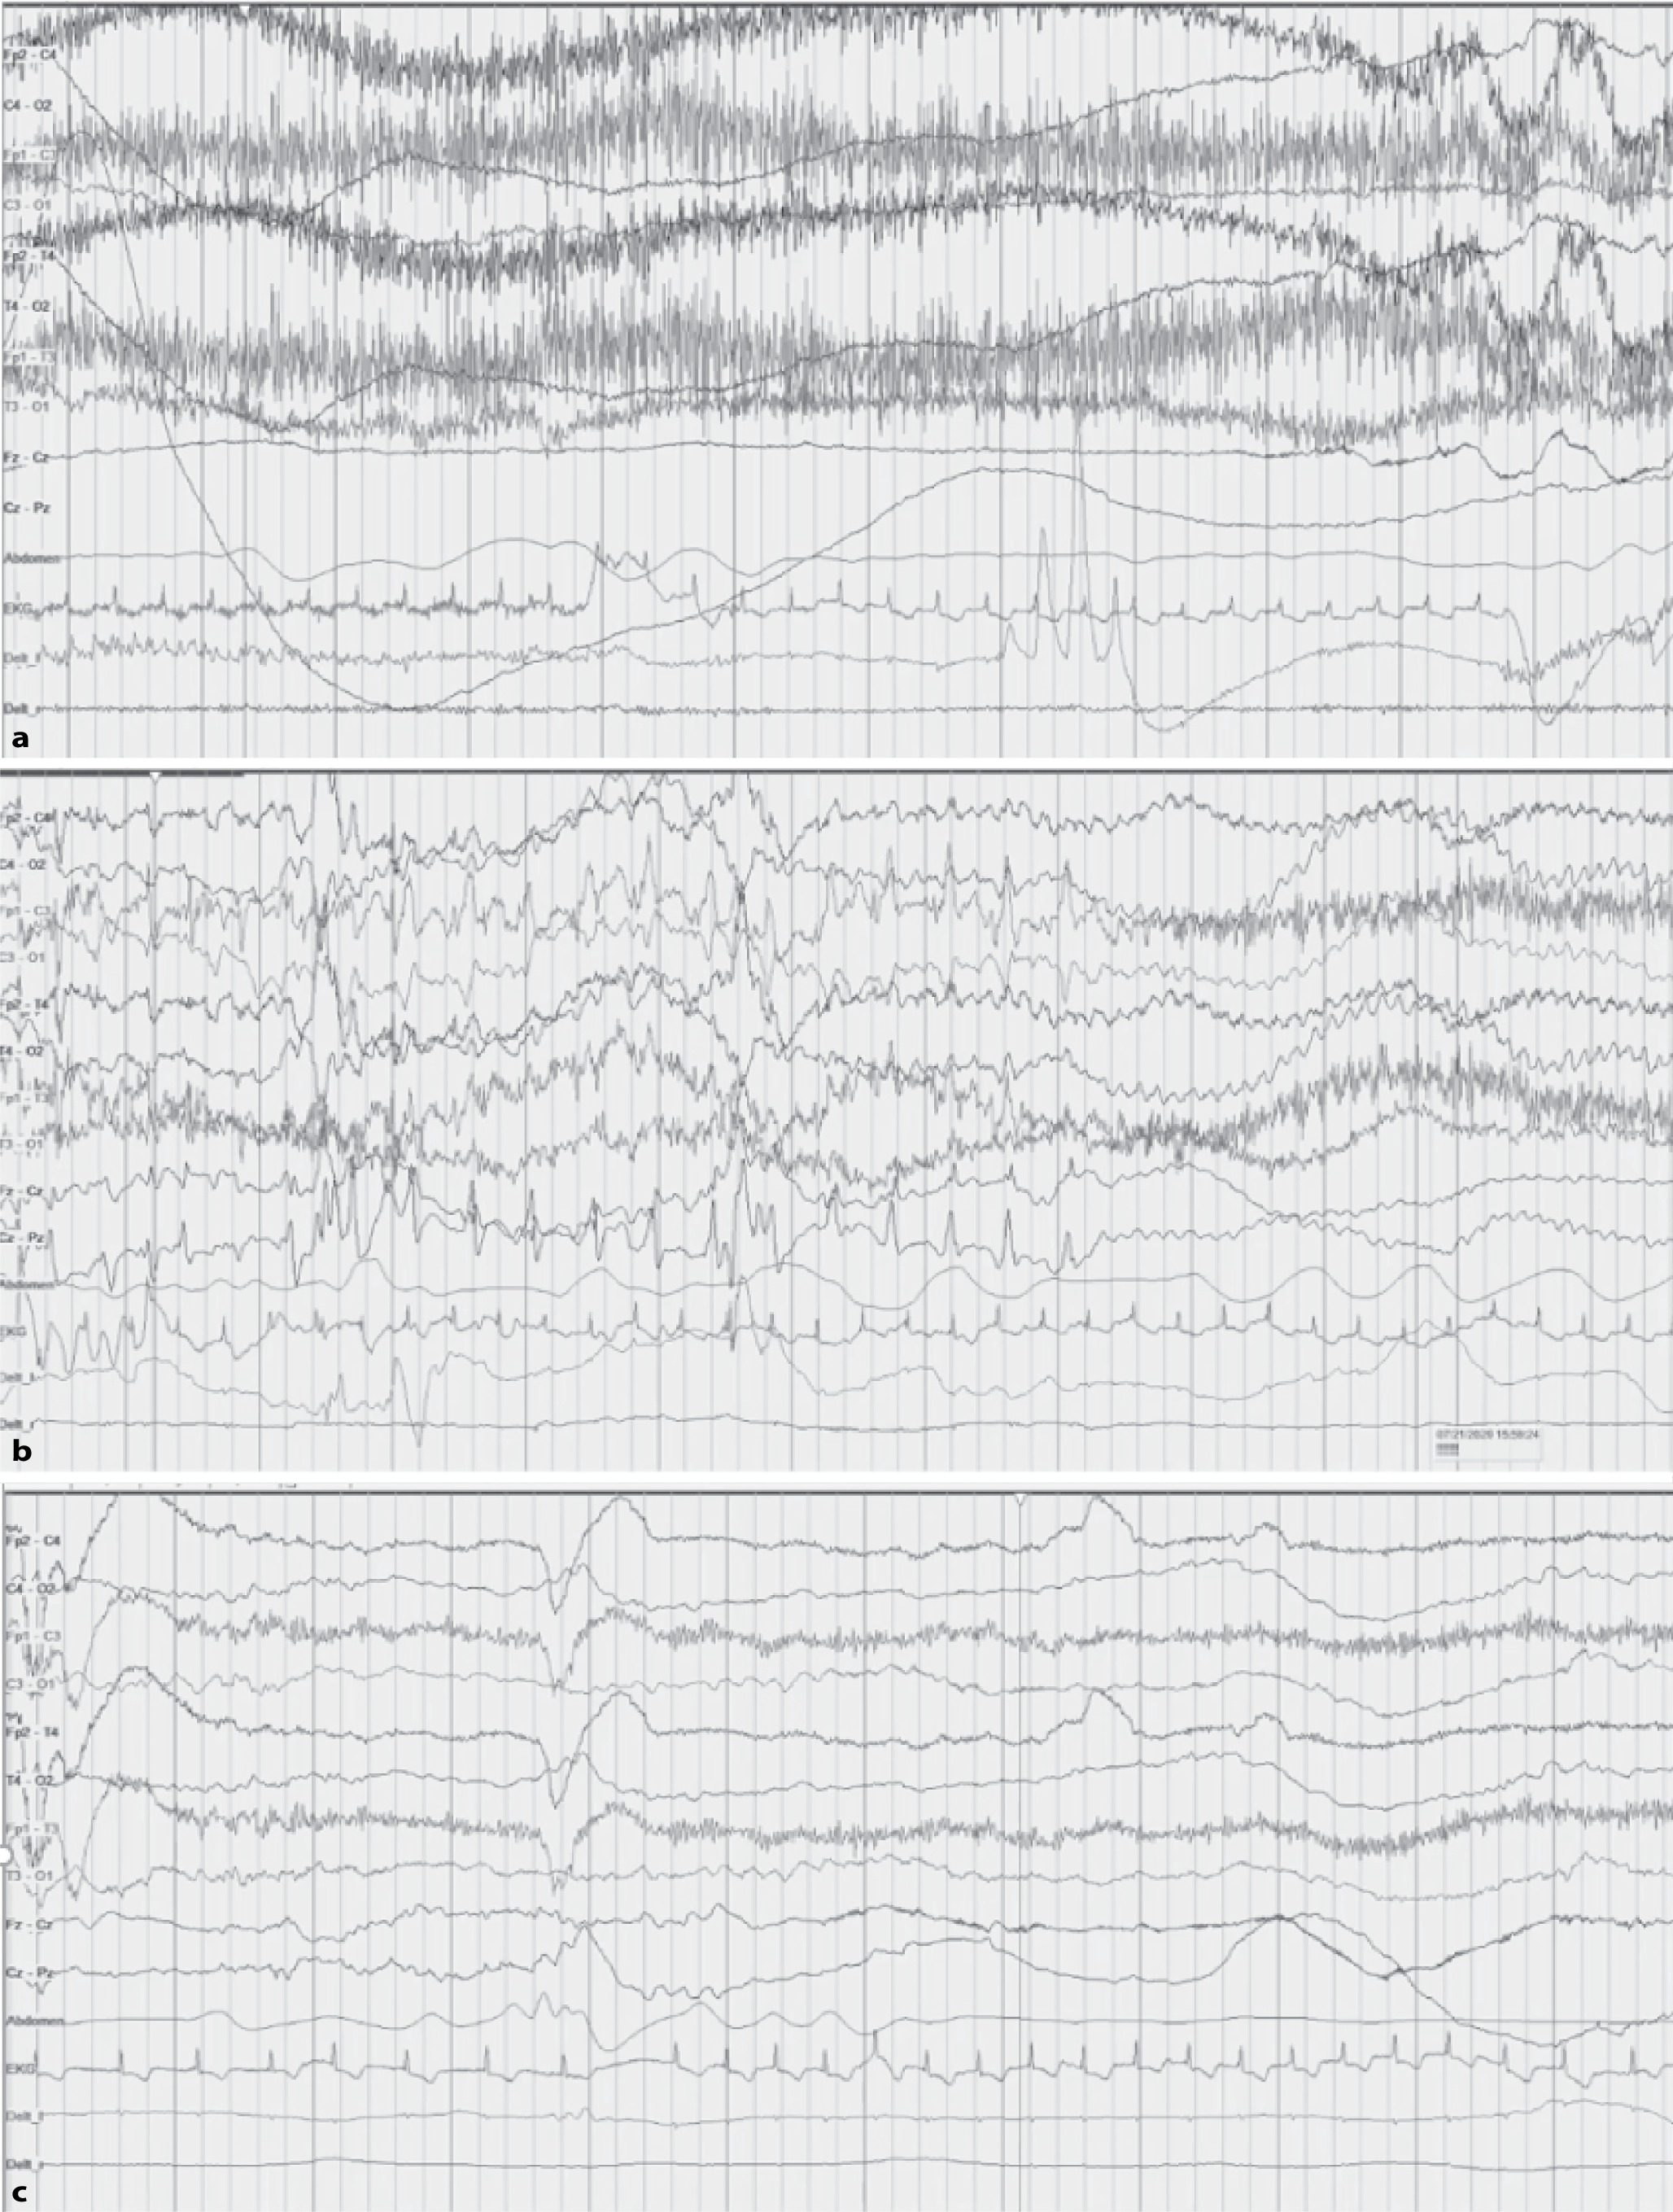

Various interictal patterns are possible, but typically a burst-suppression pattern is seen, i.e., high-voltage burst activity (150–300 µV) consisting of spikes, sharp waves, sharp and slow waves alternating with a suppressed phase (amplitude < 5 µV). The duration of the suppressed phase is also influenced by the administration of barbiturates, for example, or by the child’s state of alertness. However, discontinuous patterns, multifocal spikes, sharp waves, sharp and slow waves, and diffuse slowing are also possible (examples in Figs. 2, 3, 4, 5, 6, 7, and 8).

Fig. 2

Ictal and interictal electroencephalogram (age 1 week, amplitude 15 µV): burst-suppression pattern in metabolic early-infantile developmental and epileptic encephalopathy due to a cholesterol metabolism disorder. Clinical presentation: erratic myoclonus during bursts (first half of the image), tonic seizures, and movement disorders (not shown)

Fig. 3

Interictal electroencephalogram (age 2 days, amplitude 7 µV): discontinuous background in glycine encephalopathy. Clinical presentation: focal seizures

Fig. 4

Ictal electroencephalogram (age 3 days, amplitude 7 µV): sequential seizure with a a tonic phase, b a clonic phase (first half of the image, bilateral spikes and waves) followed by another tonic phase (second half of the page, bilateral flattening of amplitude and rapid activity), and c an autonomic phase with apnea (note absence of abdominal movement in the second half of the image) due to a KCNQ2 variant

Fig. 5

Interictal electroencephalogram (age 6 weeks, amplitude 10 µV): increased beta activity due to PAFAH1B1 (LIS) variant. Clinical presentation: focal clonic seizures and behavioral arrest

Fig. 6

Interictal electroencephalogram (age 4 months, amplitude 10 µV): deterioration of the EEG with hypsarrhythmia, partly fragmented. Clinical presentation: spasms

Fig. 7

Interictal electroencephalogram (age 4 months, amplitude 10 µV): diffuse slowing with superimposed sharp waves and sharp-and-slow wave complexes in the right hemisphere due to a CDKL5 variant. Clinical presentation: tonic seizures

Fig. 8

Interictal electroencephalogram (age 6 weeks, amplitude 7 µV): discontinuous background, intermittent burst-suppression (not shown), and multifocal spikes due to a compound heterozygous RARS2 variant. Clinical presentation: focal clonic seizures, lactic acidosis, hypoglycemia